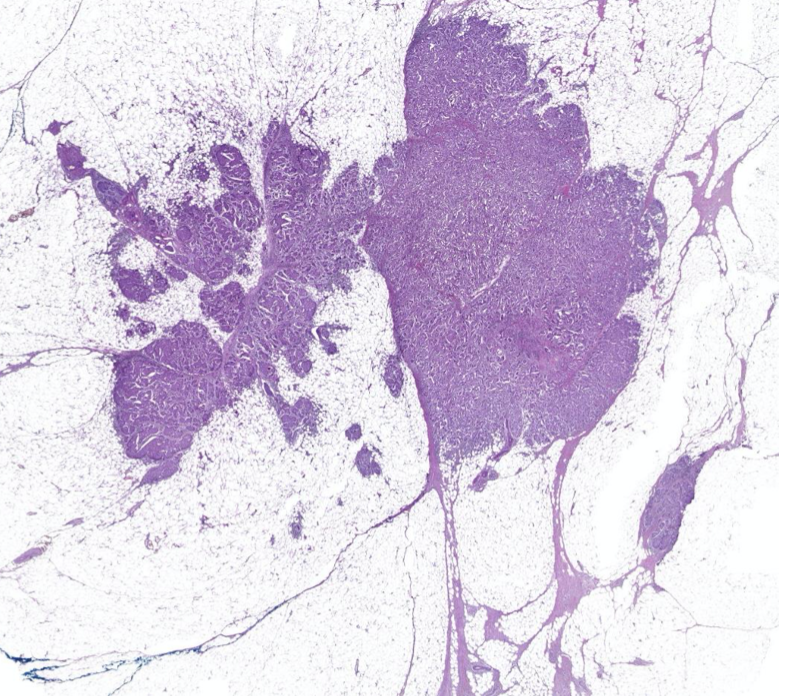

Diagnose?

Barettmetaplasie mit Dysplasie

-> Erkennt man an Becherzellen